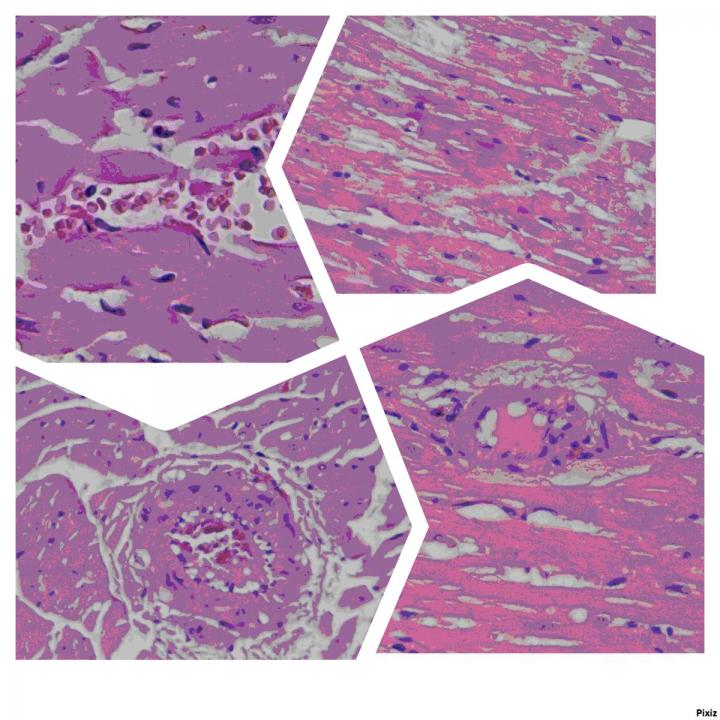

UNN researchers conducted a study of the morphological and functional state of erythrocytes and myocardial state in rats with blood loss during the posttransfusion period using ozonized erythrocyte mass.

It was shown that the use of ozonized erythrocyte mass increases the electronegativity of erythrocyte membranes, reduces their aggregation, and increases the intensity of metabolic processes in erythrocytes. By compensating acute blood loss with ozonized erythrocyte mass, it is possible to reduce the degree of manifestations of tissue hypoxia, as the rheological properties of blood and microcirculation of the myocardium improve during the posttransfusion period.

"During the posttransfusion period, myocardial microcirculation enhanced through the use of ozone limits the damage to the architectonics of the microcirculation bed and cardiomyocytes in the myocardium and facilitates the rapid and total recovery of the structural integrity of heart-cell organelles. Our research shows that ozone treatment of erythrocyte mass for transfusion has a cardioprotective effect," concludes Anna Deryugina.